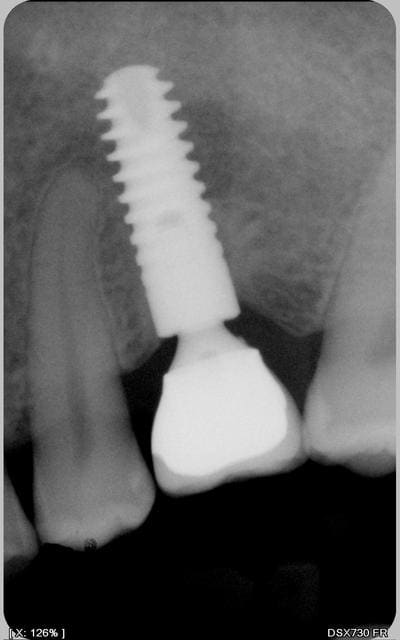

Je revois la patiente aujourd'hui et voila la radio: l'image suspecte a disparu presque complètement, implant complètement silencieux et fixe... todo isso e muito bem!!!

Y'a quand même un tissus fibreux non osseux, mais l'implant a suffisament d'os ailleurs autour de lui pour tenir le coup quand même.

P'être bien que ça ne bougera jamais, mais une RX tout les ans me semble assez raisonnable, juste au cas où...

oui Chicot mais s'agit il de fibres ou d'os moins dense ? les limites ne sont plus nettes comme au début.

ben au bout de 2 ans je dirais.......fibrose !